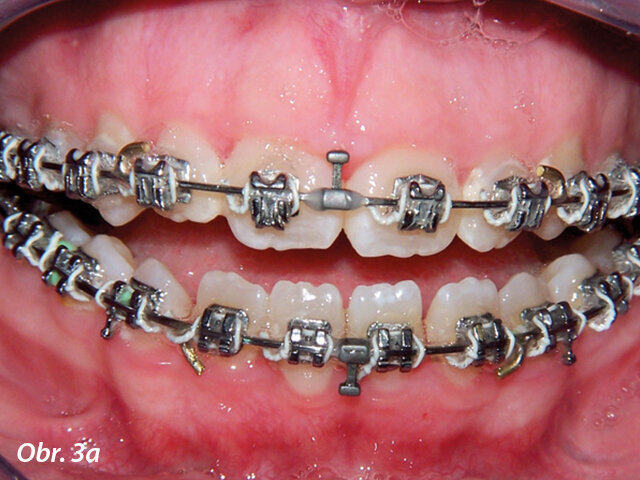

Hyperplazie gingivy před ošetřením.

Gingivoplastika týden po operaci.